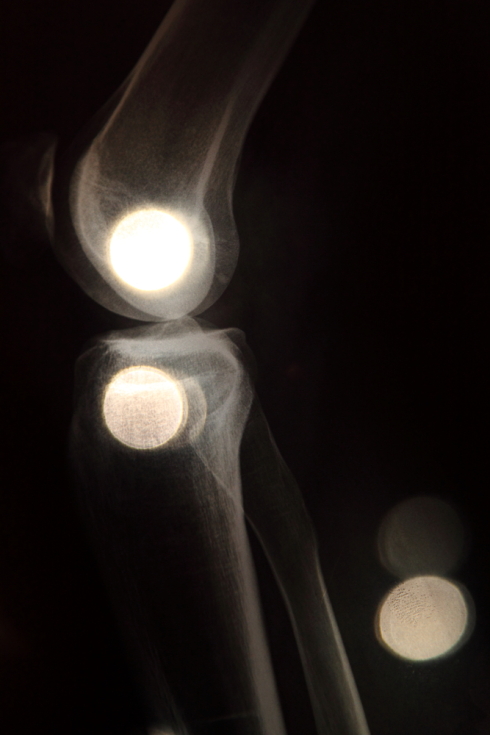

Photo works